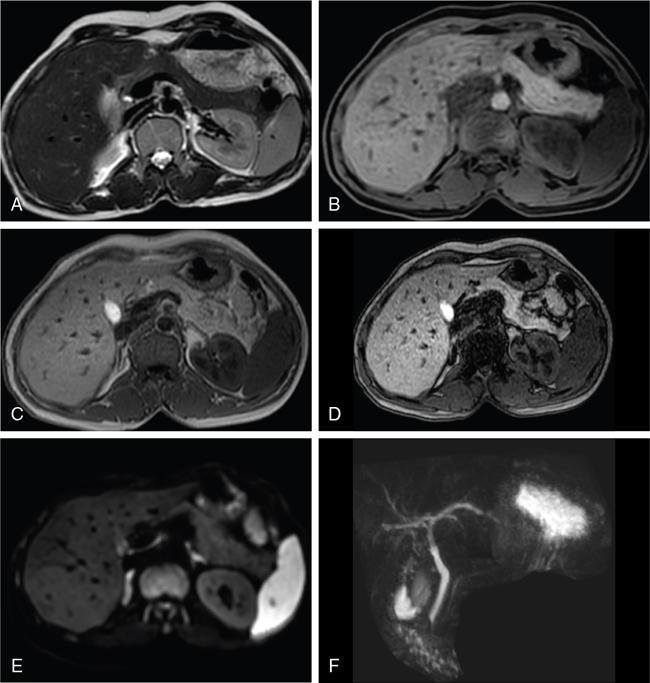

Ritu K. Kashikar, Shrinivas B. Desai, Pooja Punjani Vyas, Nilesh Doctor, Vivek Shetty Advancement and extensive use of imaging in recent times has to lead to increased detection and recognition of cystic pancreatic masses. Imaging however, plays a vital role in noninvasive diagnosis of these lesions, avoiding unnecessary intervention and planning management and follow up guidelines. The aetiology of pancreatic cysts ranges from primary cystic neoplasm to cystic degeneration of solid neoplasm to nonneoplastic cysts (Table 9.19.1). Cystic tumours of the pancreas comprise around 10%–15% of cystic lesions of the pancreas. The aim of this chapter is to educate the reader regarding imaging features of cystic lesions of pancreas, how to differentiate between cysts which can be left alone and those that require further management and also emphasize on latest international guidelines used in stratification of these lesions. Cystic pancreatic lesions are often incidentally detected on USG abdomen performed for other reasons. Although USG is an excellent modality for evaluation of cystic lesions elsewhere, it is unable to adequately characterize pancreatic cysts due to retroperitoneal location of the organ and other confounding factors such as obesity and gases. Most lesions detected on USG require characterization with either MDCT or MRI with MRCP. CEUS improves accuracy in the differentiation between a solid and a cystic lesion and also in determining whether enhancing septa or nodules are present within the cystic lesion. Currently USG also does not have a role in follow up algorithms of pancreatic cystic lesions. Multidetector CT evaluation of pancreatic lesions is best performed with a multiphasic technique (Table 9.19.2). The phases include a precontrast scan, an early arterial angiographic phase, a pancreatic parenchymal phase, and a portal venous phase. The precontrast scan is important for detection of calcification, which may be diagnostic of some lesions. Mucinous cystic neoplasms may be hyperdense on nonenhanced scan suggesting mucin content or haemorrhage. The arterial phase aids in detection of hyperenhancement neovascularity and arterial involvement in pancreatic masses. Optimal parenchymal enhancement of the pancreas is achieved at 35–45 seconds after initiation of injection of contrast agent. This is the pancreatic parenchymal phase. It is in this phase that the tumour pancreas contrast is maximum (Fig. 9.19.1, Table 9.19.3). Most hypoenhancing pancreatic lesions are best detected in this phase. The portal venous phase allows in detection of venous involvement and hepatic metastasis. Delayed phase is typically not required in cystic masses. MDCT has an accuracy of 56%–85% for characterization of cystic pancreatic lesions. MR imaging affords the best noninvasive means for the evaluation of cystic lesions of the pancreas due to superior soft tissue resolution. The helpful distinguishing characteristics of cystic pancreatic lesions, morphology of septae, relation to pancreatic duct are easier to detect at MR imaging and MR cholangiopancreatography (MRCP) than at CT (Table 9.19.4). Studies however indicate that MDCT and MRI are comparable in identifying malignant behaviour of cystic pancreatic lesions. The MRI protocol for evaluation of cystic lesions of pancreas includes T2-weighted single-shot fast spin-echo, T1-weighted in-phase and opposed-phase gradient echo, diffusion-weighted imaging, T2-weighted fat-suppressed fast spin-echo. Three-dimensional T1-weighted fat-suppressed spoiled gradient-echo T2-weighted MRCP. Postcontrast protocol includes dynamic three-dimensional T1-weighted fat-suppressed spoiled gradient-echo (in arterial, pancreatic and portal venous phases) (Fig. 9.19.2, Table 9.19.3). DWI has not found much utility in cystic neoplasms owing to overlap in ADC values. Some studies suggest role in distinguishing malignant from benign tumours in the case of mucinous cystadenoma and IPMN. Secretin is a peptide hormone produced in the intestinal mucosa, which stimulates the secretion of bicarbonate-rich fluid into the pancreatic ducts and transiently increases the tone of the sphincter of Oddi. The increased fluid distention of the pancreatic duct allows better study of ductal anatomy and identifying communication of pancreatic cystic lesions with the pancreatic duct. EUS is excellent in characterization of cystic lesions of pancreas. The proximity between the transducer and the lesions allows precise definition of the structural component of the cysts and components such as small mural nodules are better visualized with EUS than with other modalities. The other advantage of EUS is that cysts fluid aspiration and cytology can be performed. Tumour markers, genetic markers can be evaluated in the aspirated fluid. This allows comprehensive evaluation of cystic lesion. EUS also has therapeutic advantages allowing endoscopic draining of pseudocysts. Recently endoscopic ablation of cysts has been performed. These advantages have led to increasing use of EUS in recent years. This modality is however not indicated in all lesions and imaging should be able to stratify lesions requiring further invasive investigations. Studies have found PET CT comparable to PET alone or CT to determine presence of malignancy in cystic lesions. False positive findings may however be problematic. There is however no consensus for routinely using PET CT in characterization of cystic pancreatic masses. Serum CA19-9 and CEA are routinely done in all pancreatic masses. Though role in cystic lesions is still controversial. Serous cystadenoma is a benign neoplasm composed of glycogen-rich epithelial cells that form innumerable small thin-walled cysts containing serous fluid. It is the prototype microcystic pancreatic neoplasm. They occur frequently in older women (median age, 65 years) and is also called as grandmother lesion. Approximately 40% of pancreatic serous cystadenoma arise from the pancreatic head and uncinate process and 60% arise from the pancreatic body and tail. Serous cystadenomas are usually discovered incidentally at imaging; however, those that are large may cause symptoms. Patients may present with abdominal pain, palpable mass, anorexia, fatigue/malaise, or weight loss. Rarely the patient may present with jaundice. Genetic alterations similar to those in VHL are seen in sporadic SCA and include tumour suppressor gene VHL mutations and overexpression of vascular endothelial growth factor (VEGF). Allelic loss in chromosome 3 have seen in up to 40% cases of sporadic SCA. Serous cystadenomas are variable in size. The size ranges from <0.1 to 25 cm. The tumours are grossly well demarcated from the surrounding parenchyma. The gross appearance of the lesions is variable. It could be microcystic, consisting of innumerable small cysts giving the macroscopic appearance of a sponge or honeycomb. The presence of multiple, microscopic SCN is characteristic of von Hippel–Lindau (VHL). This variety show a centrally located area of fibrotic scar. In Macrocystic/oligocystic variant, borders with the surrounding parenchyma are less defined and the cystic lesion generally does not exhibit a central scar. The Solid variant, the lack of cystic spaces on gross inspection often gives the initial impression of a neuroendocrine or solid pseudopapillary neoplasm. Serous cystadenomas show nonviscous, clear-to-yellow cyst fluid, which provides an important clue to the distinction of SN from mucinous neoplasms. In contrast to intraductal papillary mucinous neoplasm, there is no connection with main or branch pancreatic ducts. These are clinically benign pancreatic epithelial neoplasms exhibiting serous morphology, characterized by a monotonous, cuboidal epithelial cell proliferation with marked cytoplasmic clearing due to intracellular glycogen. The centrally located epithelial cell nuclei are uniformly round to ovoid and not particularly large or hyperchromatic. Abundant diastase-sensitive cytoplasmic glycogen is highlighted by a periodic acid–Schiff stain. These lesions do not show evidence of necrosis, infiltrative architecture, or lymphovascular/perineural invasion, and mitotic figures are generally not observed. A variably prominent pseudocapsule of fibrosis divides parenchyma from the neoplasm On USG the microcystic variant shows lobulated contour with multiple tiny anechoic cysts separated by septae. the central scar containing calcification can be seen if present. Extremely microcystic, honeycomb variant may resemble a solid lesion at conventional US. The macrocystic type, can be mixed type with multiple large (>20 mm) and small cysts, and the unilocular type, which is more difficult to differentiate from mucinous cystadenoma (MCA). Enhancement of the intralesional sepatations is seen on contrast-enhanced USG allowing better characterization of the lesion. The central scar can show homogenous enhancement. Honeycomb variety appears as a hypervascular lesion owing to its extremely microcystic morphology and may resemble solid masses like neuroendocrine tumours. Pancreatic serous cystadenoma can have a varied appearance on CT depending on the morphologic patterns. Serous cystadenomas are typically solitary but may be multiple in von Hippel–Lindau disease, causing an appearance of disseminated involvement (Table 9.19.5). As mentioned previously, the polycystic pattern is the most common appearance of serous cystadenoma. A pattern of a bosselated collection of cysts that usually number more than six is seen. Each cyst may range from a few millimetres to 2 cm in size (Fig. 9.19.5). The other classic CT features include a lobulated contour and presence of a central stellate scar with calcification. This scar is seen in 30% cases and when present is strongly suggestive of the diagnosis. The intralesional fibrous septae show early enhancement after contrast administration. This is a distinguishing feature, as serous cystadenoma is the only hypervascular lesion among the cystic pancreatic neoplasms. Tiny cysts mimicking a honeycomb are the hallmark of this variant and may be poorly depicted as individual cysts on CT. On unenhanced CT, the honeycomb pattern may appear as a well-marginated lesion with soft tissue or mixed attenuation, depending on the size of the cysts and the amount of fibrous tissue. Moderate to strong enhancement is seen in these lesions (Fig. 9.19.6). This appears as a unilocular cyst or it may contain fewer large (>2 cm) cysts. Imaging Features include a lobulated contour, lack of a prominent thickened peripheral wall, and location in the head of the pancreas (Fig. 9.19.7). Owing to its supreme soft tissue resolution, MRI is the modality of choice in diagnosis of serous cystadenomas. The classic MRI features of microcystic variant includes a lobulated lesion with multiple small T2 hyperintense and T1 hypointense cysts with intervening hypointense fibrous sepate. These lesions do not communicate with the pancreatic duct; hence no dilatation is usually seen. Dilatation of pancreatic duct has however been reported in larger lesions. After the administration of gadolinium, the hypervascularization of the central scar and of internal septa may be seen. The morphology of the honeycomb pattern may also be better depicted on MRI. Multiple tiny T2 hyperintense cysts with intervening hypointense septae are seen (Fig. 9.19.8). The oligocystic variant shows fewer larger T2 hyperintense and T1 hypointense cysts and can mimic mucinous cystadenoma. However, the lobulated contour, together with the absence of wall enhancement and a wall thickness less than 2 mm, suggest the correct diagnosis (Fig. 9.19.9) (Table 9.19.6). The differential diagnosis of serous cystadenoma depends on the variety and are listed in Tables 9.19.7 and 9.19.8. Lesions with classic imaging features do not require further investigation or fluid analysis. The fluid in classic cystadenomas is yellow in colour and does not show elevated amylase, mucin or tumour markers. Approximately 20%–50% cases show cytological positivity for periodic acid-Schiff and cytokeratin AE1 and 3. Hemosiderin laden macrophages also do not have high diagnostic accuracy and are seen in only about 43% cases. Current management guidelines suggest (Table 9.19.9). Resection involves distal pancreatectomy or Whipples, depending on location of the tumours and is currently reserved for truly symptomatic cases. Mucinous cystic tumours are a rare subset of cystic neoplasms, constituting approximately 2.5% of pancreatic exocrine tumours. TABLE 9.19.10 The defining and characteristic histopathologic feature of mucinous cystic neoplasms (MCNs) is the presence of ovarian-type stroma similar to that observed in biliary cystadenomas. International Association of Pancreatology recommend that all suspected MCNs be surgically resected. A significant female predilection is seen with approximately 99.7% cases seen in women. As opposed to serous cystadenomas these lesions occur in middle aged women and hence the term mother lesions is used to describe these. The approximate age of occurrence is 50 years with a range from 20–82 years. Mucinous cystic tumours are a dominant cyst that is round or oval and is encapsulated. MCNs may grow slowly over time, at an average rate of 4 mm per year. The most common locations are the pancreatic body and tail (up to 75%). Stromal elements similar to ovarian stroma are the hallmark and key feature that aids in differentiation from IPMN, whose stromal elements are ductal in origin. Tall columnar cells with intracellular mucin arranged in a single row or vertically, forming papillary or polypoidal projections, constitute the epithelial elements. Portions of benign appearing epithelium can be seen adjacent to areas of invasive carcinoma in the same tumour. These lesions show smooth contour on gross appearance with few internal sepate. Peripheral calcification, mural nodule if present suggest malignant cyst (Fig. 9.19.11, Table 9.19.11). Lesions may be asymptomatic in 25% cases. Patients my present with pain in abdomen. Mucinous cystadenoma can also present with pancreatitis. Considering most lesions are located in distal body and tail involvement of splenic vein may lead to left sided portal hypertension. Mucinous cystic tumour is a well-circumscribed cystic mass in the pancreas. Lesions can have an irregular contour to the wall, septations, mural nodularity, and peripheral calcifications. The lesion may however be echogenic due to high by mucin content or haemorrhage which may impair the detection of other features. CEUS may improve detection rate of septa and mural nodules. Lesions are typically well-circumscribed with smooth contour. On unenhanced CT, mucinous cystadenoma may appear hypodense or slightly hyperdense content, due to the presence of variable amount of mucin and haemorrhage. Curvilinear calcifications occur along the periphery of the lesion and are seen in 15% of cases, in contrast study enhancement of the fibrous cyst wall along with enhancement of any septations or mural nodules is seen (Figs. 9.19.12 and 9.19.13).